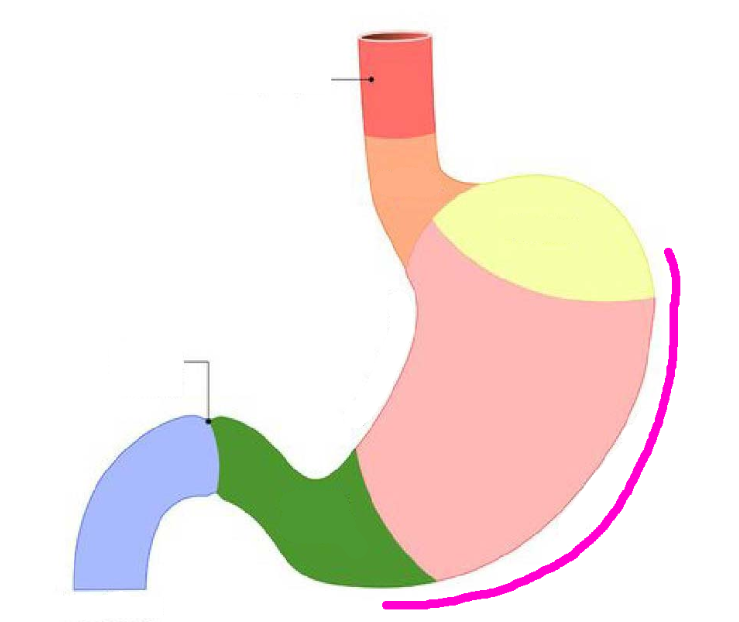

Esophagus

Diaphragm

Greater curvature of stomach

pink line

Lesser curvature of stomach

pink line

Fundus region

purple highlight

Cardia region

green highlight

Body of stomach

blue highlight

Pylorus of stomach

yellow + orange highlights

Cardiac orifice

Esophageal lumen

Pyloric sphincter

Pyloric orifice

Duodenum

blue highlight